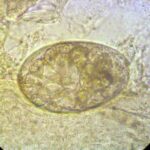

Histologic examination of a specimen containing a burrow reveals that the burrow in almost its entire length is located within the horny layer . Only the extreme, blind end of the burrow, where the female mite is situated, extends into the stratum malpighii . The mite has a rounded body and measures about 350 to 450 IJm in length and 250 to 350 IJm in width . |

In the papulovesicular form of scabies, spongiosis is present in the stratum malpighii near the mite to such an extent that formation of a vesicle is often the result. Even if no mite is found in the sections, the presence of eggs containing larvae, of egg shells, or of fecal deposits (scyballa) within the stratum corneum is indicative of scabies . The dermal infiltrate in sections containing mites shows varying numbers of eosinophils. |